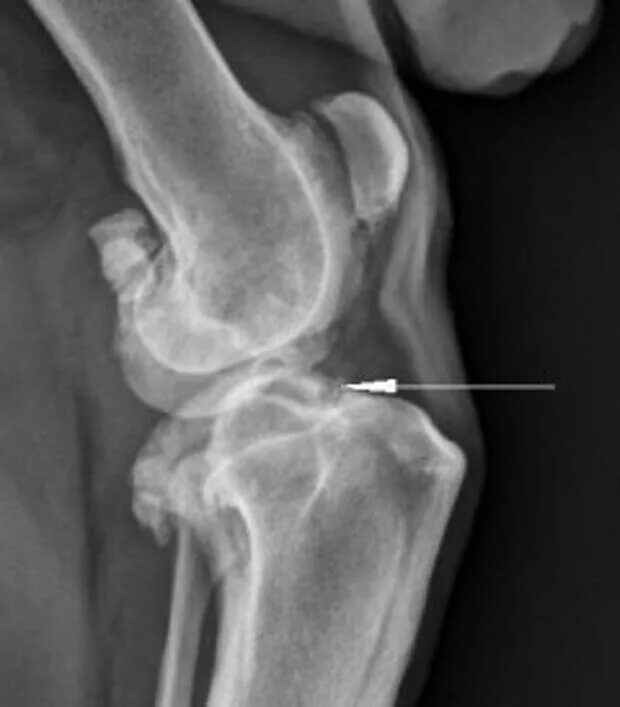

Разрыв коленного сустава 3 степени